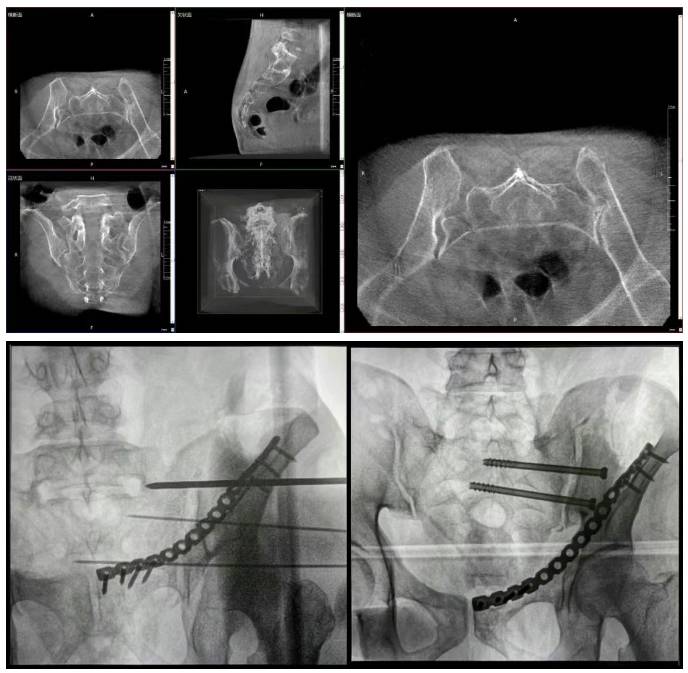

移动三维C形臂,骨科医生的第二双“眼睛”,能在术中快速地生成横断面、矢状面、冠状面断层图像和实时动态三维立体图像的X线摄影设备,其通过直观地分析病变与周围组织的立体空间关系,三维断层成像能够使手术模拟和手术方案的制定更加准确,被广泛应用于骨科、创伤科。

移动三维C形臂协同医院创伤导航机器人已开展多例“骨盆骨折微创手术”,为患者带来了更加高效的诊疗体验,为准确诊疗贡献了一“臂”之力。

移动三维C形臂术中使用图片图源来自:“上海市第七人民医院”微信公众号

普爱医疗移动三维C形臂的二维透视和术中三维成像效果,为机器人提供了准确的术中影像依据,协同提升手术整体的精度和效率,为患者带来了更安全、更高效的医疗服务体验。

移动三维C形臂影像普爱医疗移动三维C形臂采用智能变频脉冲技术、人体图形化曝光剂量预设、DAP剂量监控等多项技术,严格控制整体辐射剂量,让医生和患者在面对长时间手术时,享受创新科技带来的关怀。